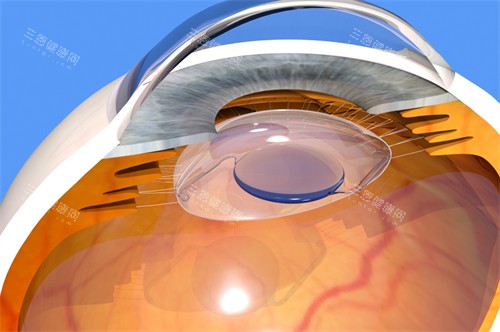

对于较高度近视(1800度以内)或角膜偏薄者,ICL晶体植入术成为“保留角膜结构”的优选。其特点包括:

材料优势:采用Collamer专有胶原晶体,生物相容性高,紫外线过滤功能可保护眼底;

可逆性:若未来视力变化或需其他治疗,晶体可取出或更换;

风险点:内眼手术对医生经验要求极高,需严格把控晶体尺寸与拱高参数。

鸡西爱尔眼科医院由集团医师主刀,术前通过IOLMaster生物测量仪、Pentacam眼前节分析仪等设备,精密计算晶体度数与拱高范围,术后拱高达标率超98%左右。